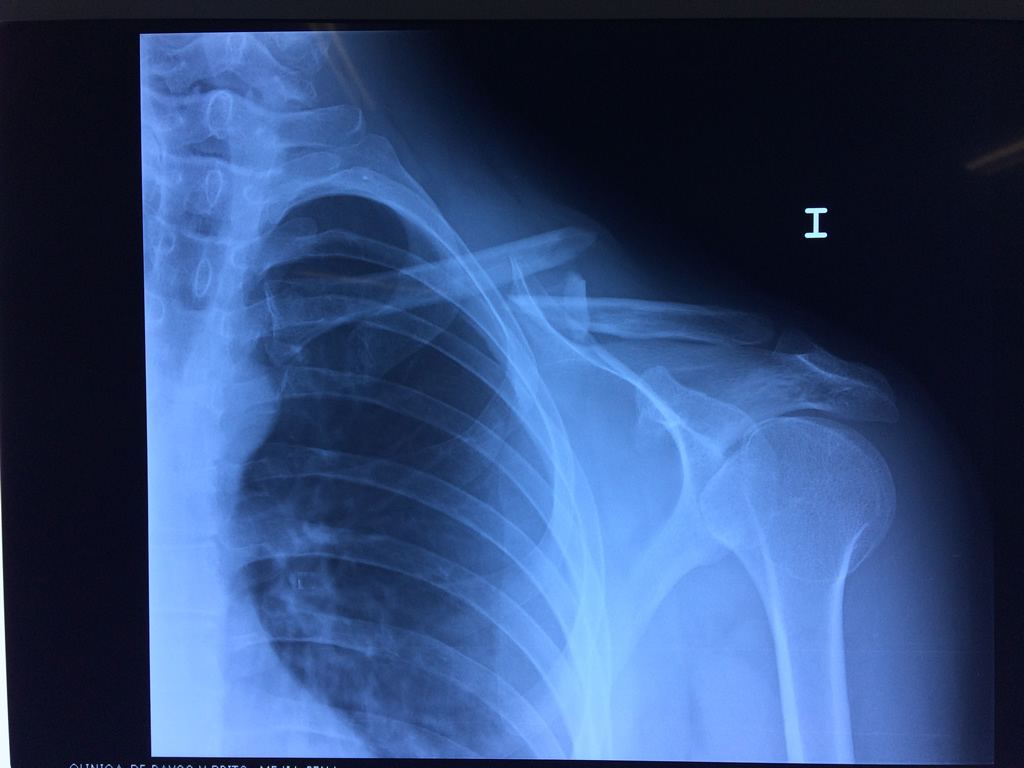

La clavícula es un hueso largo, con forma de "S" itálica, situado en la parte anterosuperior del tórax. Junto con la escápula forman la cintura escapular. Se puede palpar por toda su longitud y se extiende del esternón al acromion de la escápula, siguiendo una dirección oblicua lateral y posterior.

Se considera el único medio de unión entre el miembro superior y el tórax. A pesar de su aspecto, similar al de un hueso largo, posee una estructura semejante a la de un hueso plano, ya que carece de epífisis y de diáfisis, lo que la harían entrar dentro de la clasificación de hueso largo. Carece de un canal medular propiamente dicho.